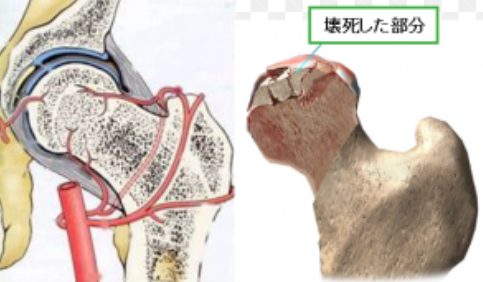

特発性大腿骨頭壊死症

特発性大腿骨頭壊死症は、血液が行き渡らなくなることで骨が壊死し、そこが突然に骨折して、股関節が痛くなる希少疾患です。現在(2017年)、国の難病にも指定され、原因究明や治療方法などさまざまな側面から研究されています。

血液の流れが悪くなることによって、骨が死んでしまう

特発性大腿骨頭壊死症とは、骨の一部である大腿骨頭の血流が悪くなることによって壊死し、最終的には壊死部の骨折や骨頭の圧潰を起こす疾患です。大腿骨頭は、股関節にある大きなボール状の骨のことを指し、骨盤と大腿骨をつなぎ、上半身の体重を支える役割をしています。

骨は他の臓器などと同じく、血液によって栄養を与えられています。そのため血流が何らかの理由によって滞ると、心筋梗塞や脳梗塞と同じように、血流が骨に行き渡らなくなり、骨が死んでしまうのです。

骨の壊死は「腐る」わけではない

「壊死」という言葉を耳にすると、糖尿病患者さんの「壊疽(えそ)」のように体の一部が腐り、切断しなければならないといったイメージを抱く方も多いかと思います。しかし、骨の壊死はこのイメージとは異なります。

骨は新陳代謝を繰り返し、日々吸収され、新たに作られています。しかし骨が壊死すると骨が吸収されたきり再生されず、結果その部分の骨が脆くなって、骨折や圧潰を引き起こします。 骨の壊死はすべて体のなかで起きることなので、ばい菌が繁殖して腐敗するようなことはありませんし、そのため足を切断する必要もありません。この疾患を理由に命を落とすということはまずないので、安心していただきたいと思います。

骨折、骨の圧壊による痛み

特発性大腿骨頭壊死症の症状は、大腿骨頭のある股関節に生じる痛みです。ここでは痛みのメカニズムについて説明します。

何らかの原因で血流が滞り、骨に栄養がいかなくなると、骨が壊死してしまいます。骨が壊死すると、体は「壊死した骨を再生しよう」という指令を出し、壊死した骨を吸収し、再生させようとします。

ご存知の通り、骨は骨折した骨を元どおり直すため、多少の再生能力を持っています。しかし、その再生能力はそこまで強い力ではなく、壊死した骨を100%元どおりにすることはできません。

そのため、一度骨が壊死するといずれ再生が追いつかなくなり、もろくなった骨が体の重さに負けて骨折してしまったり、丸い部分が圧潰して変形してしまい、痛みを伴うようになるのです。